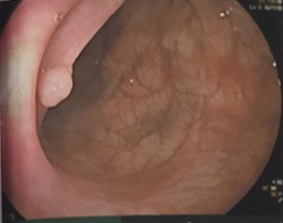

UNG THƯ DẠ DÀY KHỞI PHÁT SỚM Ngày đăng: 22/01/2026 Theo Globocan 2022, ung thư dạ dày đứng thứ 5 về tỷ lệ mắc và tỷ lệ tử vong, với 968 784 ca mắc mới và 660 175 ca tử vong. Bệnh tiến triển thầm lặng, các triệu chứng ban đầu thường mơ hồ và không...